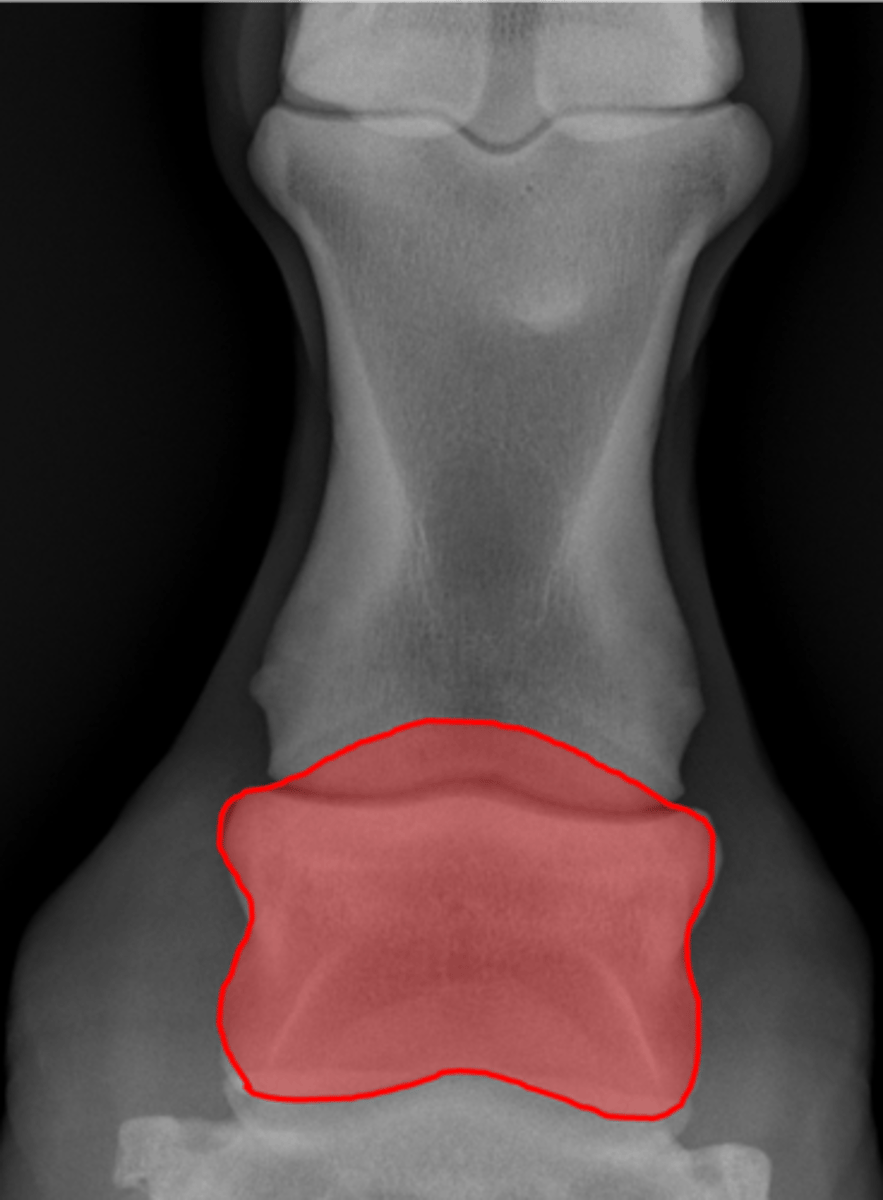

Coffin bone (P3)

Palmar process of P3

Extensor process of P3

Navicular bone

Coffin joint

Coffin bone

Navicular bone

Crena

Vascular channelsv

Solar canal